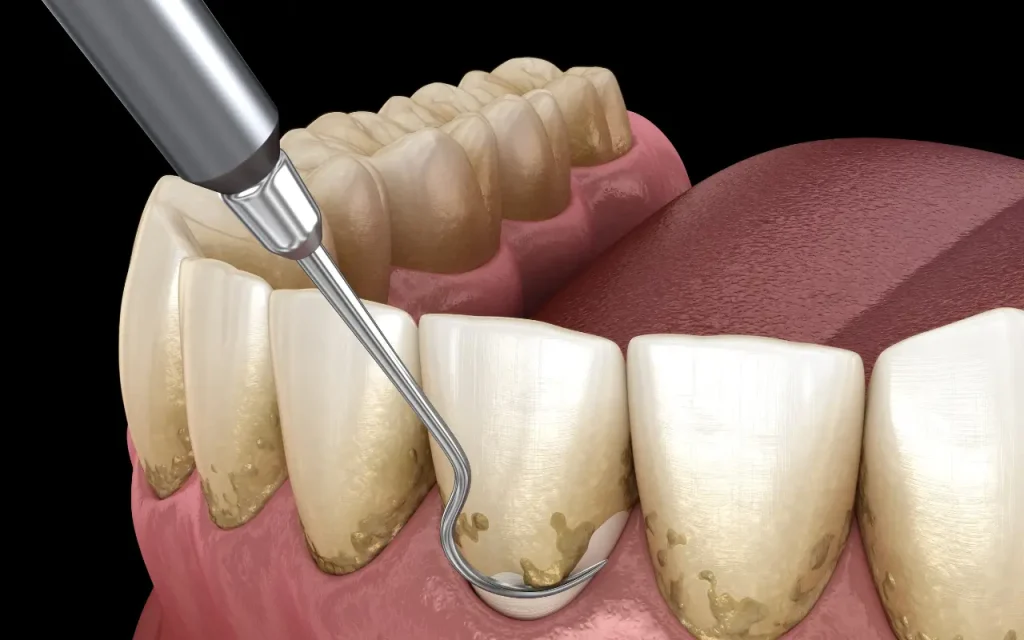

การรักษาในระยะเริ่มต้น

ในระยะเริ่มต้นของโรคปริทันต์ การรักษาที่พบบ่อยคือการขูดหินปูนและการเกลารากฟัน (scaling and root planing) ในกระบวนการนี้ ทันตแพทย์จะใช้เครื่องมือเพื่อขูดคราบหินปูนและคราบจุลินทรีย์ที่ติดอยู่บนฟันและรากฟันออก ซึ่งช่วยลดแหล่งสะสมของเชื้อโรคและลดการอักเสบของเหงือก